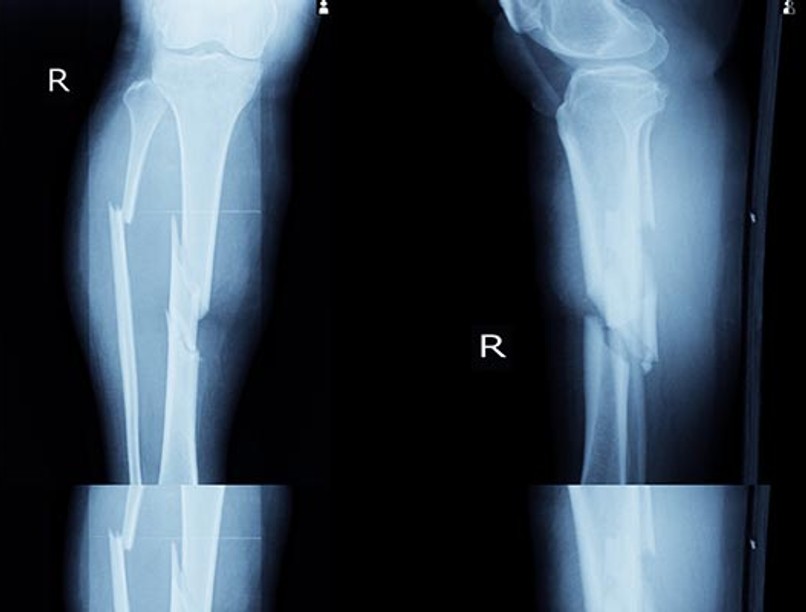

csonttores

A csonttörés felismerésében a számítógép és az orvosok egyforma hatékonysággal dolgoztak